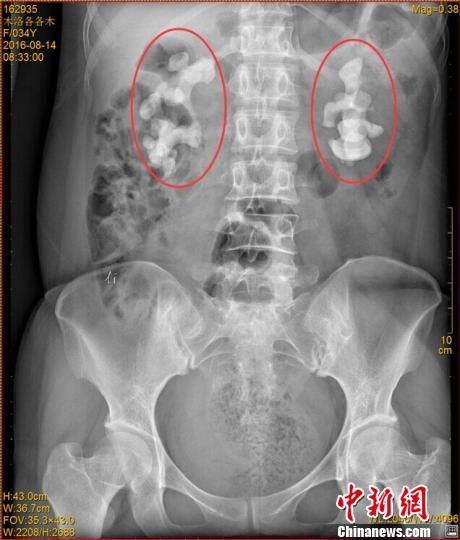

各各木術前影像圖片,紅圈內為巨大腎結石。 鐘欣 攝

中新網成都11月7日電 (王鵬)記者7日從四川省結石病醫院獲悉,該醫院近日收治了一名罕見腎結石病人。來自四川涼山的34歲女子各各木,雙腎長出10厘米巨型結石,腎內空間幾乎全被結石填滿。

“臨床上,雙腎長巨大結石的患者一般都是中老年男性,女性較為少見,年輕女性更加罕見。”四川省結石病醫院常立高醫生詳細檢查后發現,該女子雙腎內空間幾乎被結石全部填滿。他詢問患者后判斷,該罕見病例的出現與女子常年喝生水有直接關系。